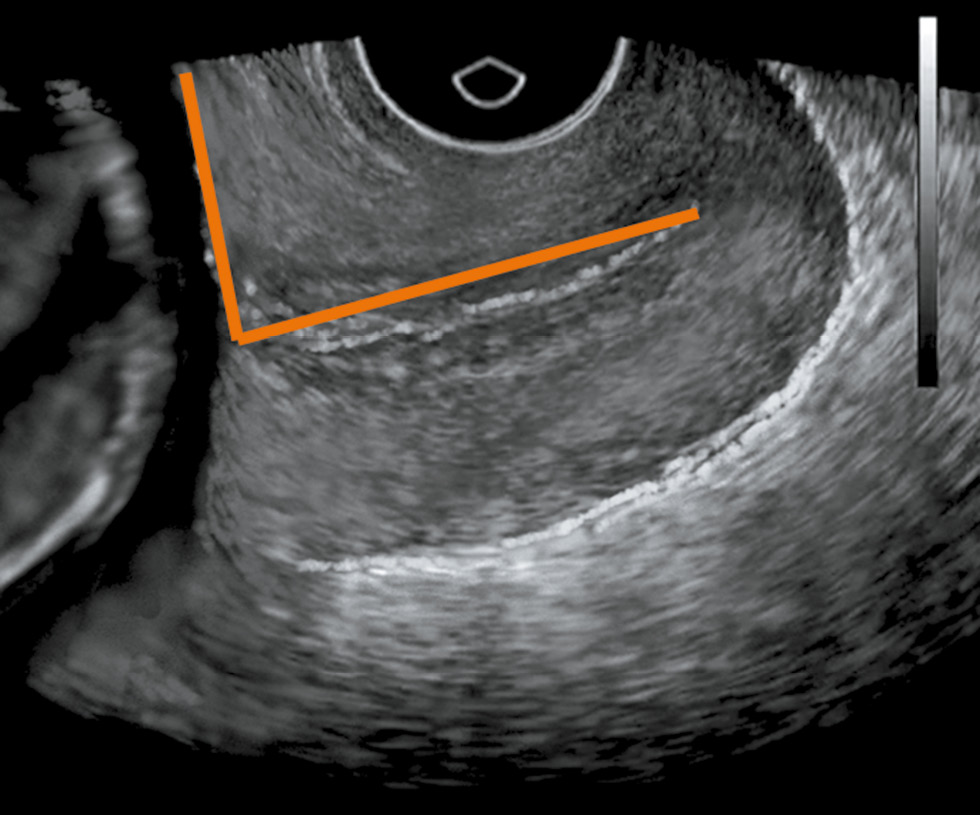

The mean SWS value in the area of the internal uterine orifice and the utero-cervical angle significantly differed in the studied groups (p < 0.05) (Table 2, Fig. 1, 2).

Fig. 1. Patient V., gestational age 28 weeks, utero-cervical angle - 106 °

Fig. 2. Patient L., gestational age 29 weeks, utero-cervical angle - 88 °

Among the pregnant women who subsequently had a preterm birth, already at 22–23 weeks of gestation, the mean SWS value in the internal uterine orifice was less than the normal values, whereas the value of the utero-cervical angle was higher compared to those who did not have preterm labor (p < 0.05). Indicators of the cervical length in the examined groups did not significantly differ.

Since the SWS values can be used to determine the elasticity of the tissue under study, a decrease in this indicator in pregnant women with subsequent preterm birth, as well as an increased utero-cervical angle, indicate cervical softening at 22–23 weeks of gestation; and at weeks 28–29, the SWS value continued to decrease, whereas the utero-cervical angle increased, which indicated cervical maturation and onset of preterm birth. Indicators, such as the mean SWS in the area of the internal uterine orifice and the utero-cervical angle, can be attributed to markers of preterm labor, which can be used to predict the development of labor.